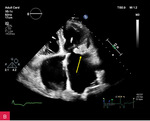

Rycina 2A, B. Zmiana u podstawy tylnego płatka mitralnego, obejmująca jego nasadę, a także fragment mięśnia ściany dolno-bocznej lewej komory w projekcji przymostkowej w osi długiej LAX (A) oraz w projekcji zmodyfikowanej, w której lepiej uwidoczniono hiperechogeniczną uwapnioną otoczkę zmiany oraz powodowany przez nią cień akustyczny (B)